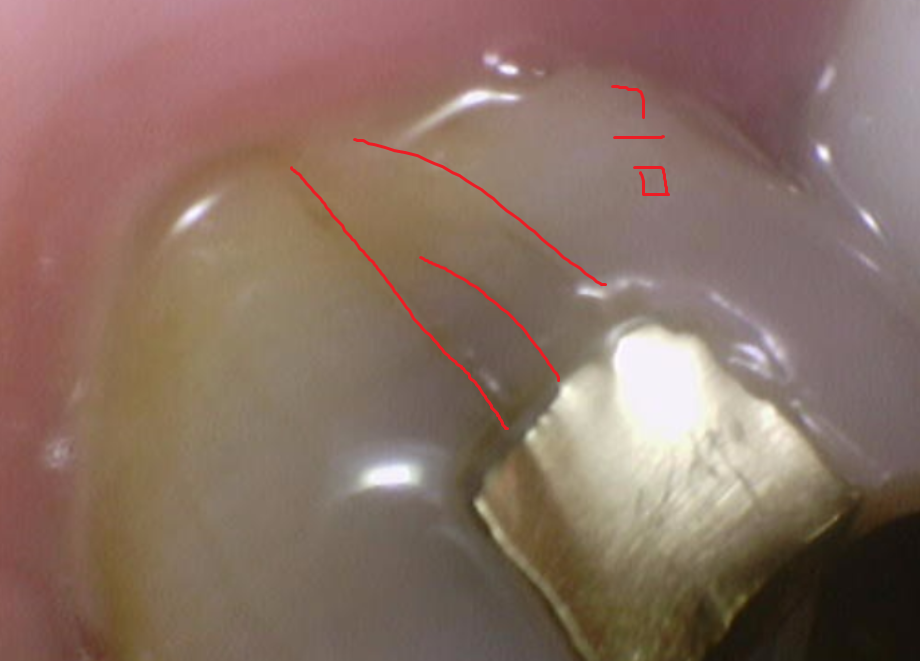

그리고 사진을 보시면 아시겠지만

치명적인 단점 두번째도 보이네요.

치아랑 딱 달라붙지 않아

씹는 힘이 가해지게 되면 치아에 금을 유발합니다.

미세한 금이요.

심한 경우 치아가 파절되기도 합니다.